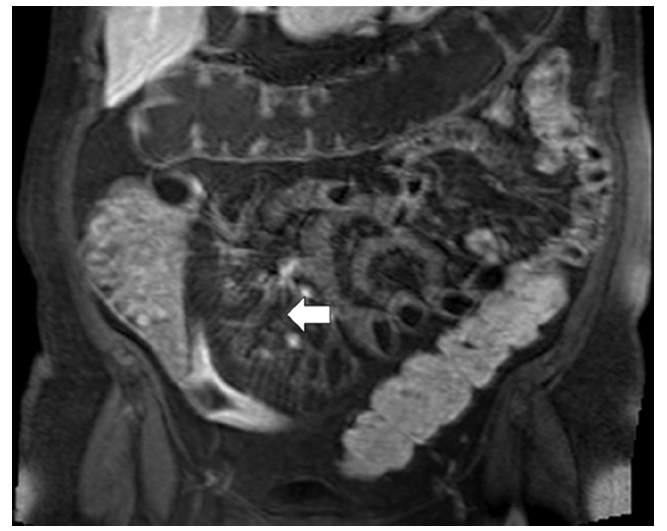

La TC permite identificar la hipervascularización del mesenterio, la elevación de la atenuación de la grasa mesentérica (20-60 UH) y el aumento en el espacio entre la vasa recta, que dan la apariencia de los dientes de un peine (Fig. 1) (3,4. La resonancia magnética (RM) también permite identificar los hallazgos que configuran el signo (Fig. 2) (3,5.

Koh et al. (2 describieron, en una serie de 30 pacientes evaluados por RM, que 18 de los 23 pacientes con enfermedad activa y 3 de los 7 pacientes con enfermedad inactiva presentaban el signo del peine, lo que corresponde a una sensibilidad del 78% y una especificidad del 57%.